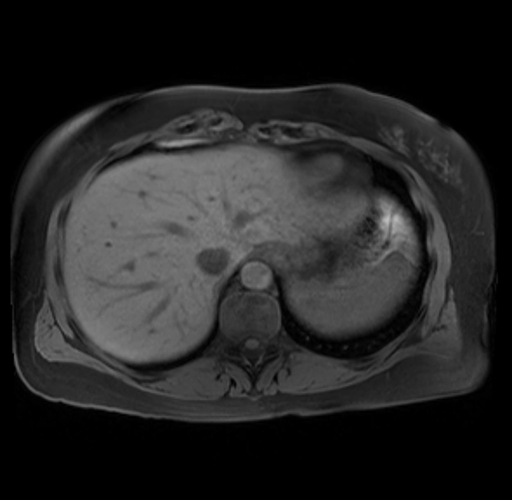

Imaging Analysis

Look through the patient's CT scan to identify any areas of concern for the necessary procedure.

Based on your CT findings, which issue(s) are present and would give reason for "planned slowing down moment(s)" in this case?

Considering a standard distal pancreatectomy procedure, what step(s) of the operation would you do differently in this case?